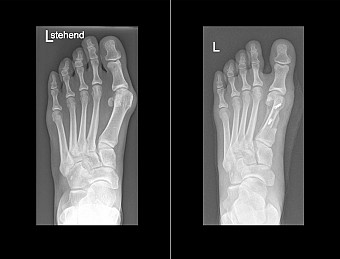

OP in Scarf-Technik vorher und nachher

Häufig wird eine Osteotomie durchgeführt: Die gezielte Durchtrennung des Mittelfußknochens an einer Stelle. Der Knochen wird wieder in seine natürliche Position gerückt, das Gelenk zentriert und die Weichteile bzw. Kapsel und Sehnen korrigiert. Für Stabilität sorgen zum Beispiel Schrauben oder Platten.